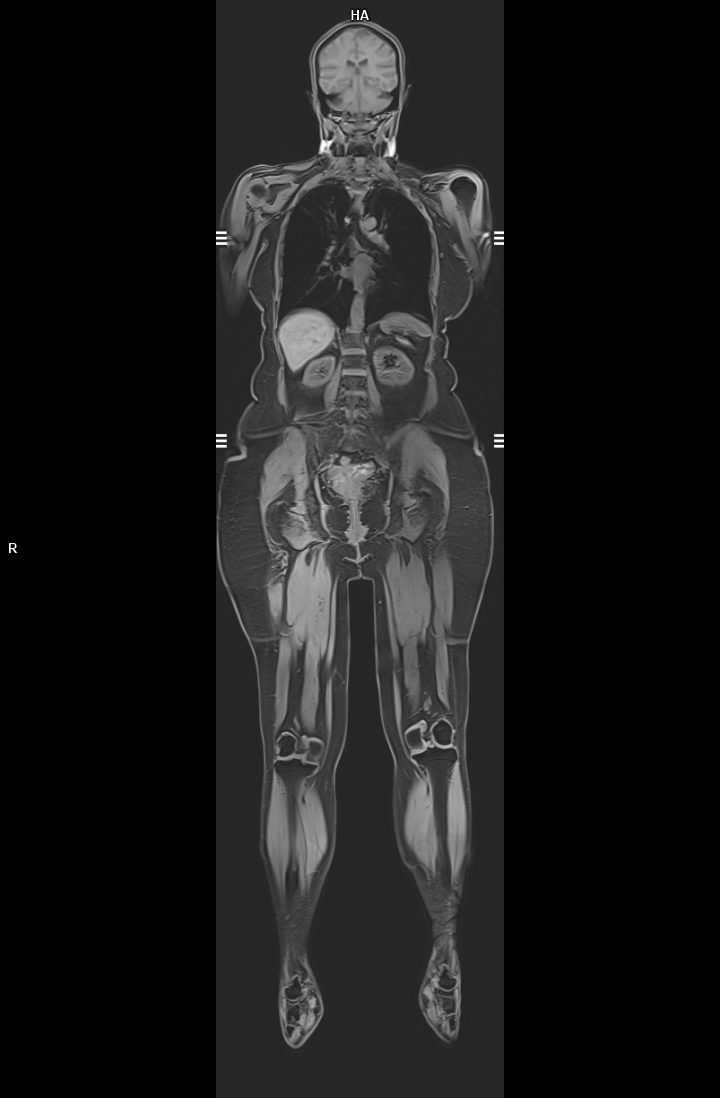

• Tüm Vücut MR

• 3 TESLA MR ÇEKİM GÖRÜNTÜLERİ

3 Tesla MR Çekim Görüntüleri

• 3 Tesla MR Çekim Görüntüleri